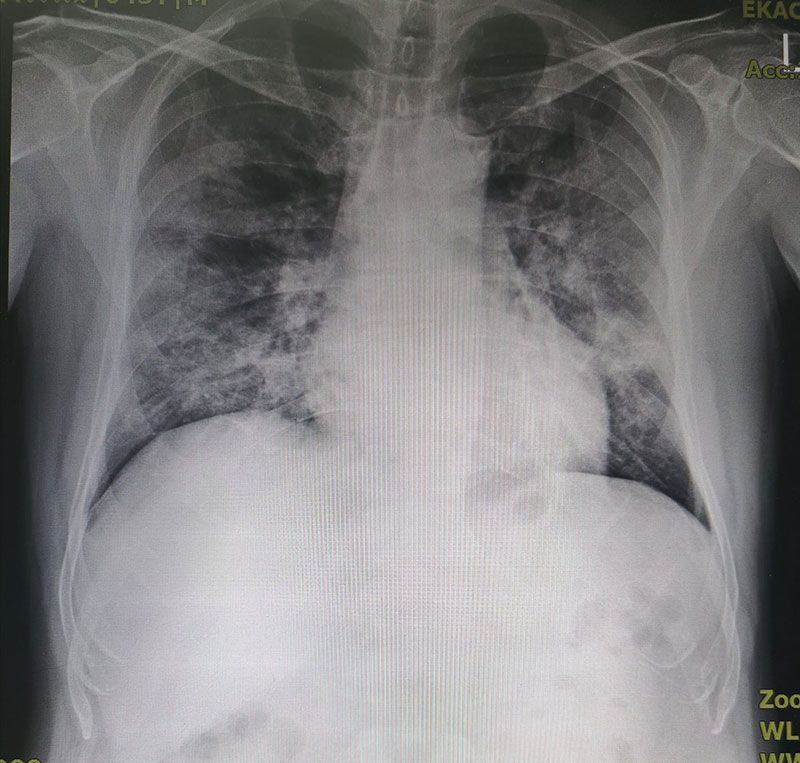

‘หมอนิษฐา’เปิดภาพปอดผู้ป่วยโควิด 9 วัน กว่าจะได้ตรวจ เนื้อปอดโดนกินไปเยอะแล้ว

ชัดเจนมากว่า ตอนนี้ทุกเคสที่มา คือมาช้ามากๆ เพราะเค้าตระเวรไปหลายที่แล้ว หาไม่ได้ สุดท้ายก็หอบ…มาถึงรพ ก็ต้องทำให้เค้าอยู่ดี แล้วผลการรักษาก็แย่เพราะมาถึงช้า นี่คือภาพฟิลม์คนไข้ ที่ ARI clinic พร้อมประวัติ ป่วยมา 9 วัน ไปที่ไหนก็ไม่มีใครตรวจให้ จนต้องมาที่นี่…..